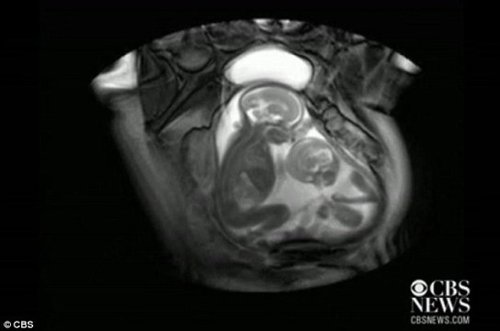

扫描发现双胞胎在子宫里“掐架”(图)

核磁共振成像技术显示,一对双胞胎在妈妈肚子里拳脚相向“掐架” 中新网12月1日电 据外媒报道,近日一段对孕期20周孕妇的核磁共振的扫描视频显示,一对双胞胎还在妈妈肚子里就开始挥动手脚 “掐架”,令人感到神奇又搞笑。 据报道,英国伦敦帝国理工学院(Imperial College)胎儿保健中心本打算用核磁共振成像仪来诊断共享一个胎盘和同一个血液供应系统的胎儿双胞胎输血症候群(twin transfusion syndrome)情况,却意外拍到了子宫中双胞胎的“大战”。 视频显示,画面右边个子稍小的胎儿在对左边稍大的胎儿挥动手脚,“拳打脚踢”,似乎打算用身体争得更多空间。而后者比较安分,也动了动嘴,缩了一下身子。 据悉,如果双胞胎中一名胎儿吸收供血过多,可能造成高血压、心力衰竭,而另一胎儿则吸收不足,如果不及时采取措施,可能会造成更严重的情况。 目前不清楚这对双胞胎的性别。